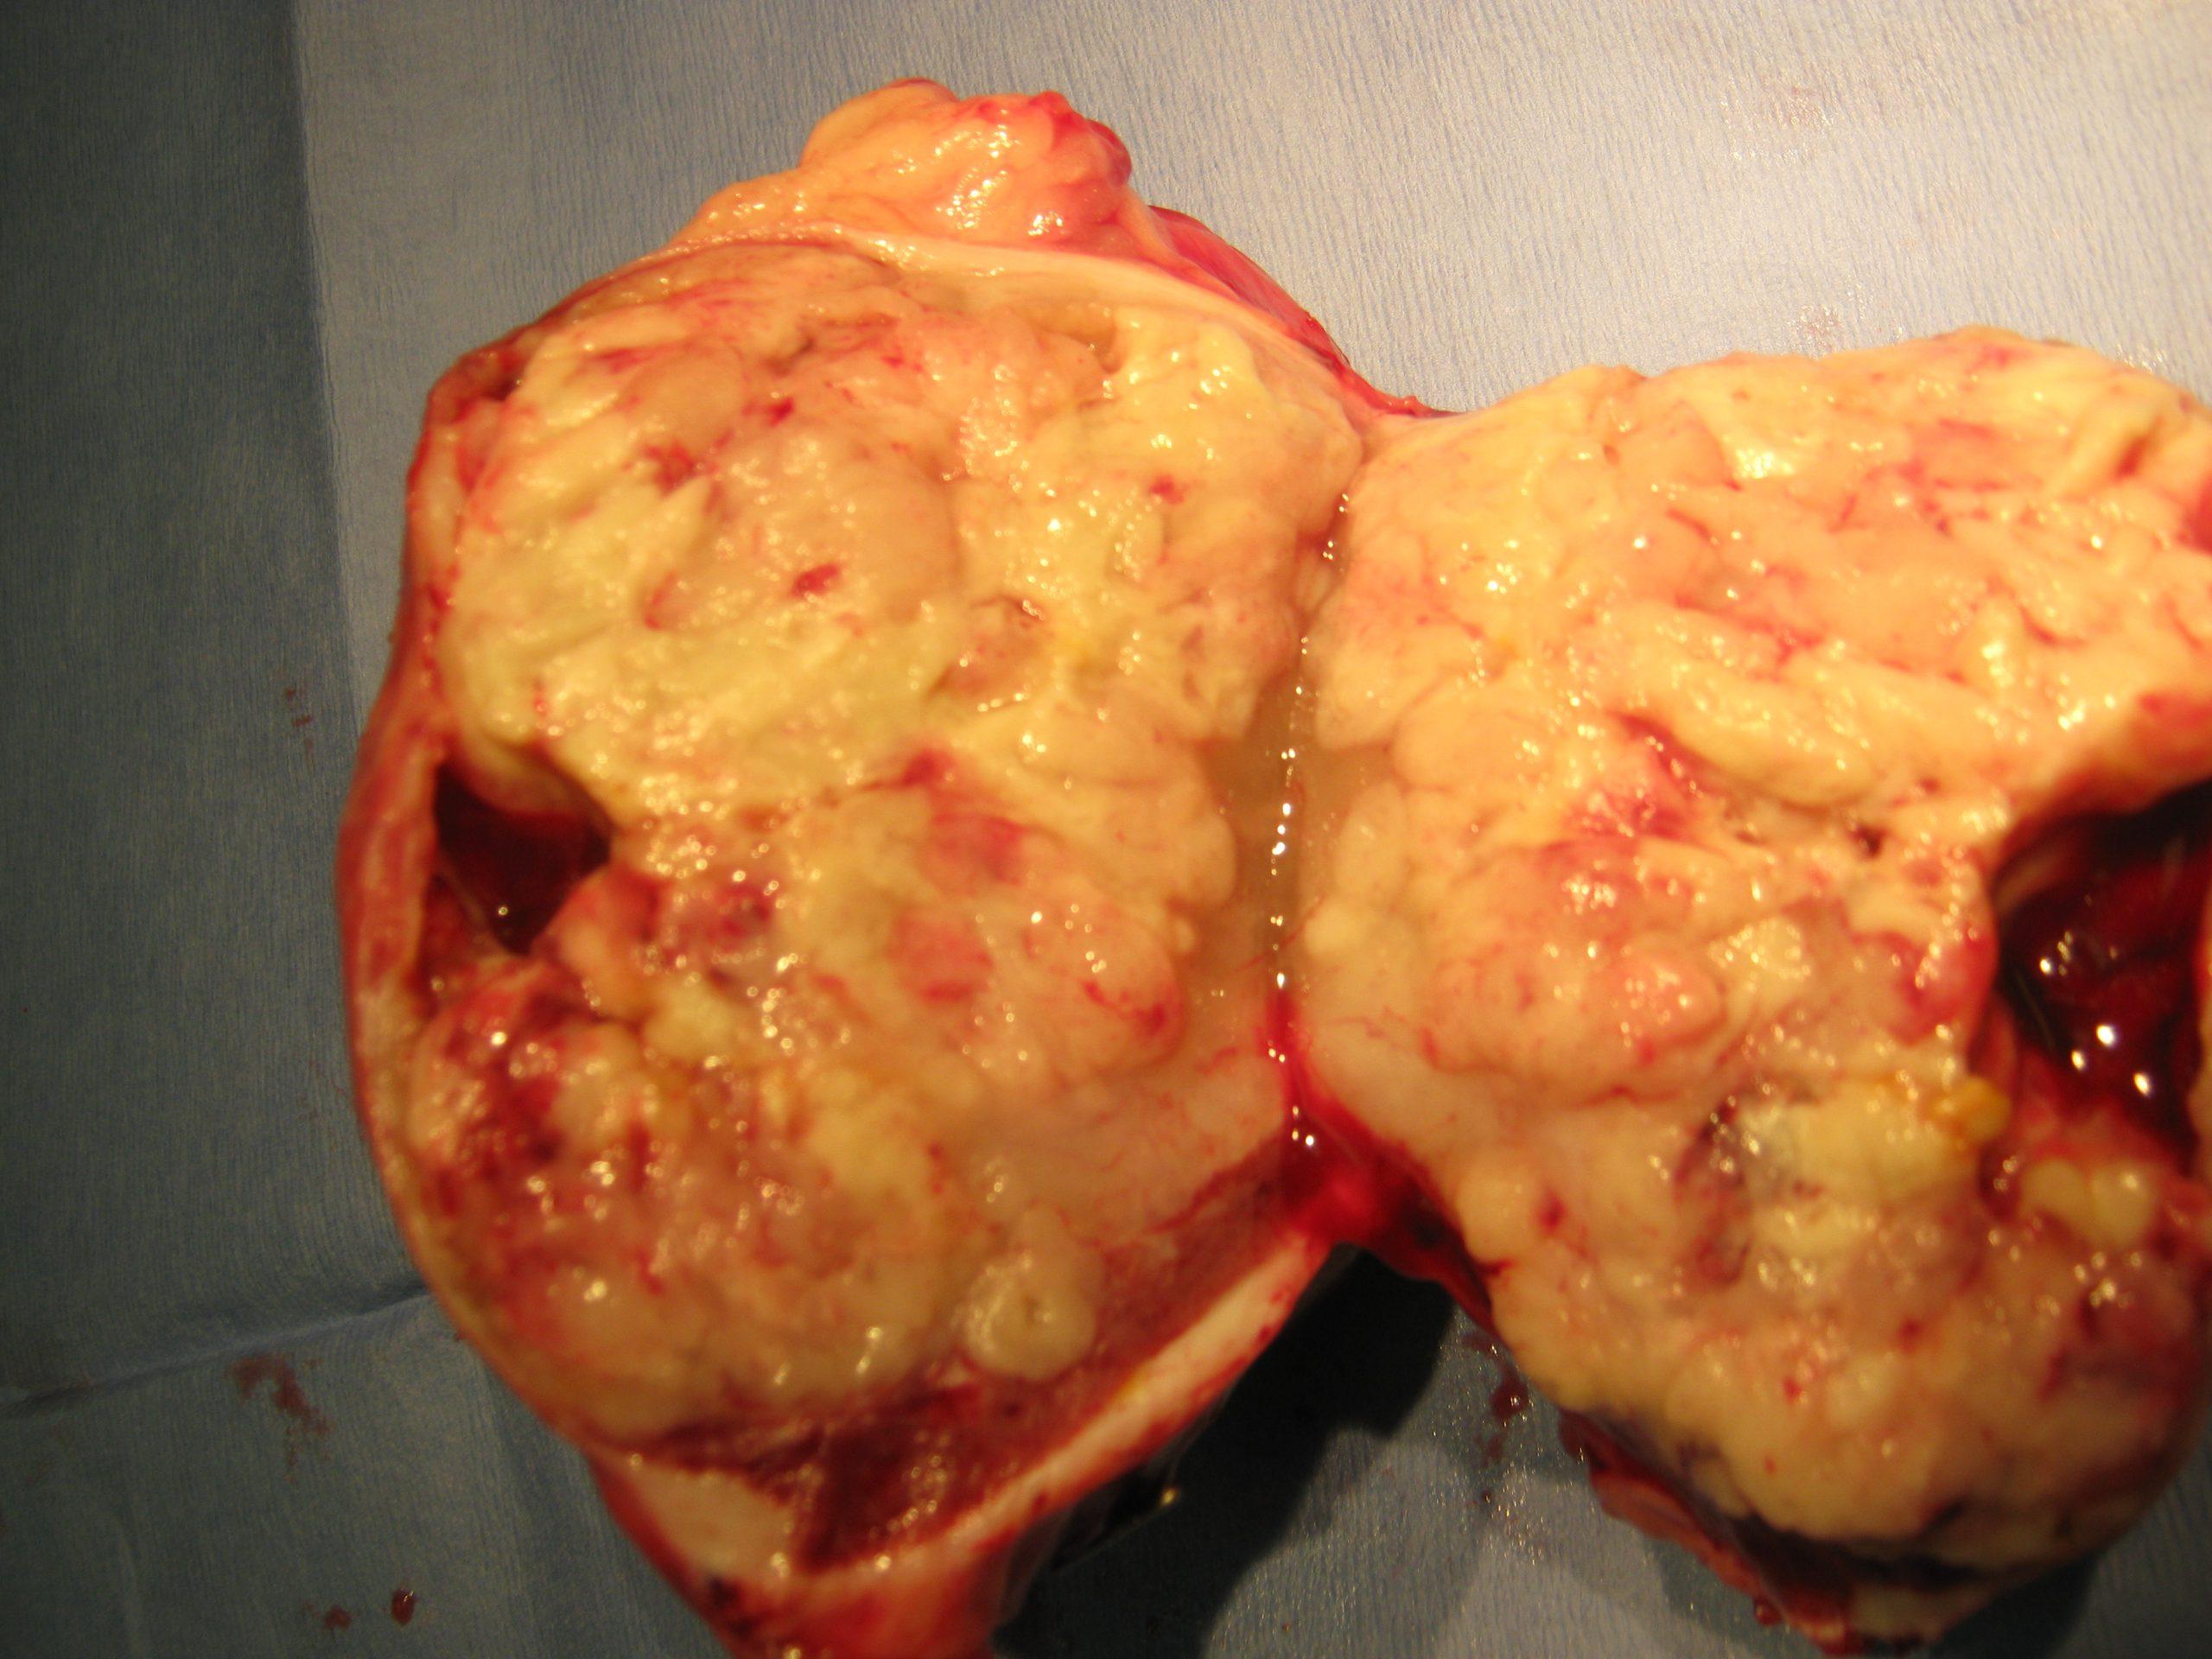

The spleen contained a mixed, echogenic complex mass that measured 10+ cm. The mass was deriving from the caudal splenic body. A large amount of free fluid was noted in the abdomen. Omental nodular changes were noted.

Splenic mass. Free fluid and omental nodular changes. Given that the patient is not overtly anemic, the abdominal fluid is likely paraneoplastic in nature. There was no obvious organ metastasis noted. However, some omental nodular changes could be consistent with seeding.

Splenic mass